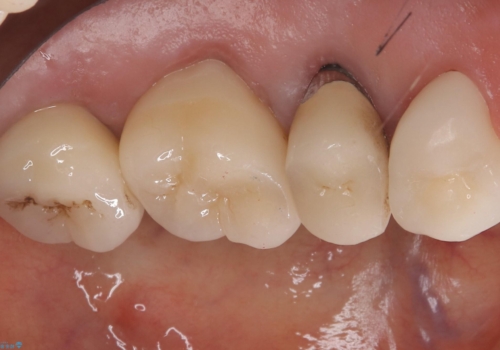

古いクラウンを除去し、不適部位から中で広がっていたカリエスを除去したのちCRにて築造、仮歯を経てセラミッククラウンをセットしています。